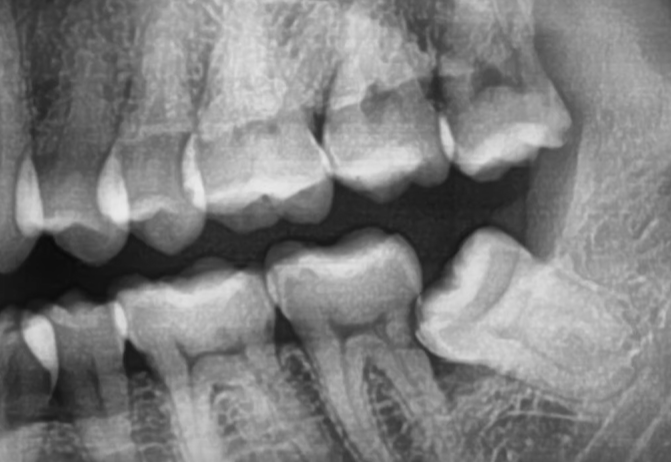

1) 단순매복: 다른 이와 같은 방향으로 자란 사랑니

2) 복잡매복: 아래 사진을 보면 사랑니가 누워있어, 그냥 뽑을 수 없는 것을 복잡매복이라 하고, 마취를 하고, 사랑니 일부를 절단한 후에 뽑는다고 하네요.

3) 완전매복: 잇몸 밖으로 나오지 않은 사랑니를 완전매복이라 하며, 앞치아에 영향이 없다면 뽑을 필요가 없을 수 있지만, 앞치아의 뿌리를 누르는 등 영향을 주고 있다면 잇몸을 절개하여 발치합니다.